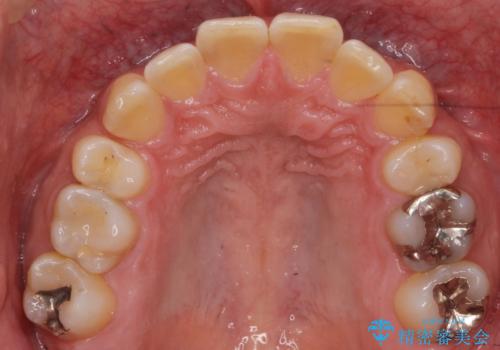

- 前歯だけ歯並びを治したいとのご希望で来院された患者様です。

数年前にワイヤー矯正を行ったものの、少し後戻りしてしまったそうです。

上の前歯が斜めに見えること、犬歯と小臼歯の間の隙間、上下顎前歯のがたつきを治すことをご希望されていました。

気になるのは前歯だけで、奥歯の咬み合わせは気にならないとのことでした。